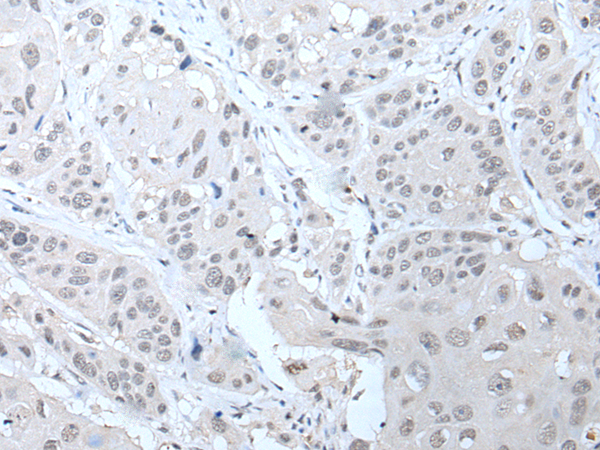

IHC positive control: |

Human thyroid cancer and human liver cancer |

IHC Recommend dilution: |

25-100 |